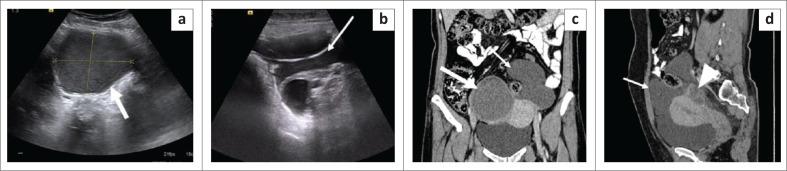

The mesentery is a broad fan-shaped fold of peritoneum that suspends the loops of small intestine from the posterior abdominal wall. Although primary neoplasms arising in the mesentery are rare, the mesentery is a major avenue for the dissemination of tumours, which can spread through hematogenous, lymphatic, direct or peritoneal seeding. Imaging helps in the diagnosis of these tumours and aids in directing appropriate treatment by assessing their size, extent and relationship with adjacent structures. The aim of this article is to describe the spectrum of imaging findings of the various mesenteric lesions using ultrasound and CT.

肠系膜是腹膜的一个宽阔扇形褶皱,将小肠袢从腹后壁悬吊起来。虽然起源于肠系膜的原发性肿瘤很少见,但肠系膜是肿瘤播散的主要途径,肿瘤可通过血行、淋巴、直接蔓延或腹膜种植扩散。影像学有助于这些肿瘤的诊断,并通过评估其大小、范围以及与相邻结构的关系来指导适当的治疗。本文旨在描述使用超声和CT对各种肠系膜病变的影像学表现范围。